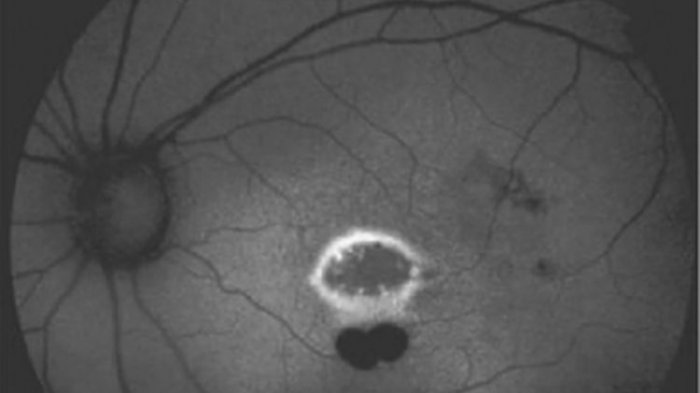

Menurut para ahli di National Eye Institute, ada lubang cukup besar di makula mata sebelah kiri anak tersebut. Makula adalah bagian dari retina yang mengatur penglihatan pusat atau kemampuan untuk melihat objek dengan lurus. Kasus yang terbit di The New England Journal of Medicine, Rabu (20/6/2018), menjelaskan, anak itu berulang kali menatap sinar laser yang berwarna hijau dari alat peraga presentasi.

Tes medis mengungkapkan, kondisi mata sebelah kanan anak tersebut normal, yaitu 20/20. Namun, mata sebelah kirinya tercatat hanya 20/100. Menurut ahli dari American Optometric Association, mata manusia dengan penglihatan 20/100 harus berdiri 6 meter untuk melihat sesuatu yang dapat dilihat dengan jarak 10 meter oleh mata normal.

Menurut laporan, kerusakan mata sebelah kiri anak tersebut cukup parah dan tindakan operasi juga belum memberikan hasil menggembirakan bagi kemampuan pengelihatan anak itu.